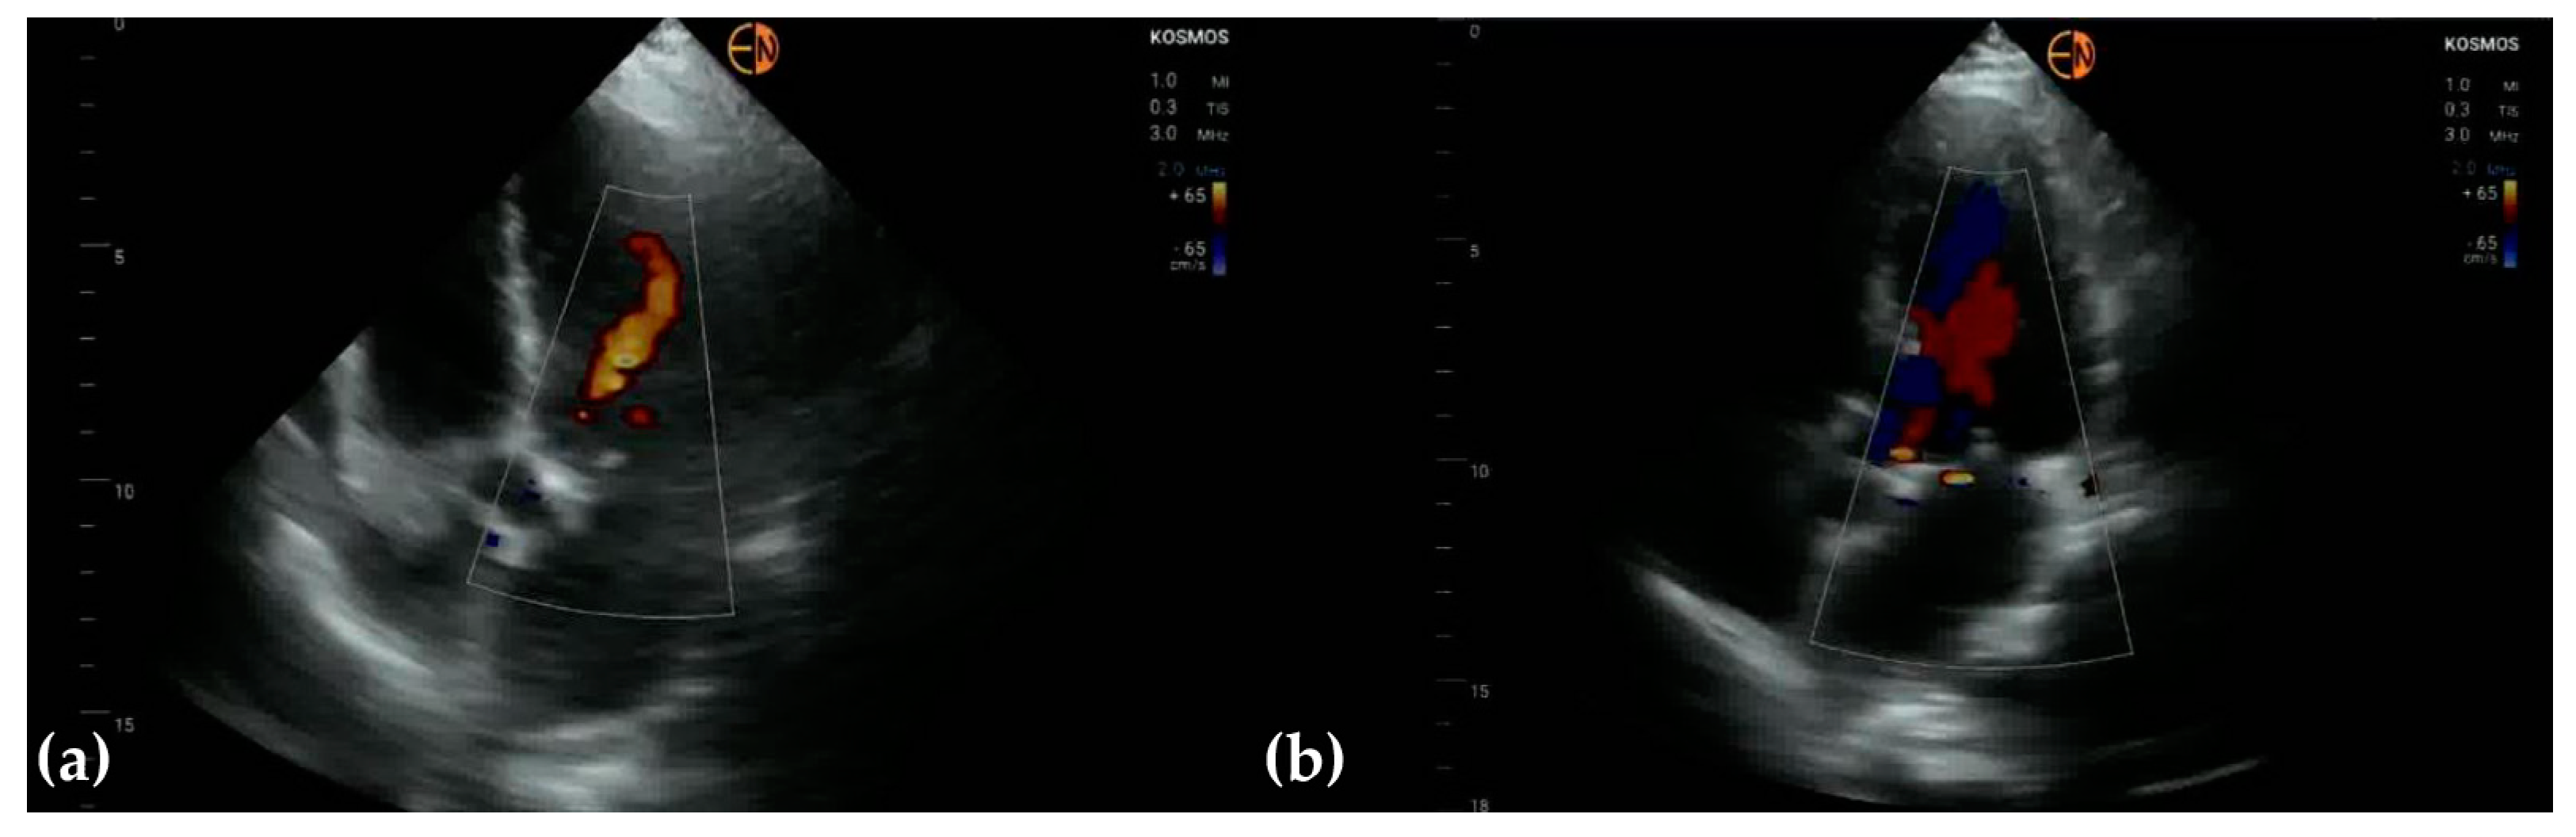

3.3. Valvular Stenosis and Regurgitation

| Mitral valve | 26 (61.9 [45.7 to 76.0]) 0.5321 [0.3451 to 0.7191] | ||

| Mild mitral regurgitation | 16 | 14 | |

| Moderate mitral regurgitation | 10 | 7 | |

| Severe mitral regurgitation | 1 | 1 | |

| Normal | 15 | 21 | |